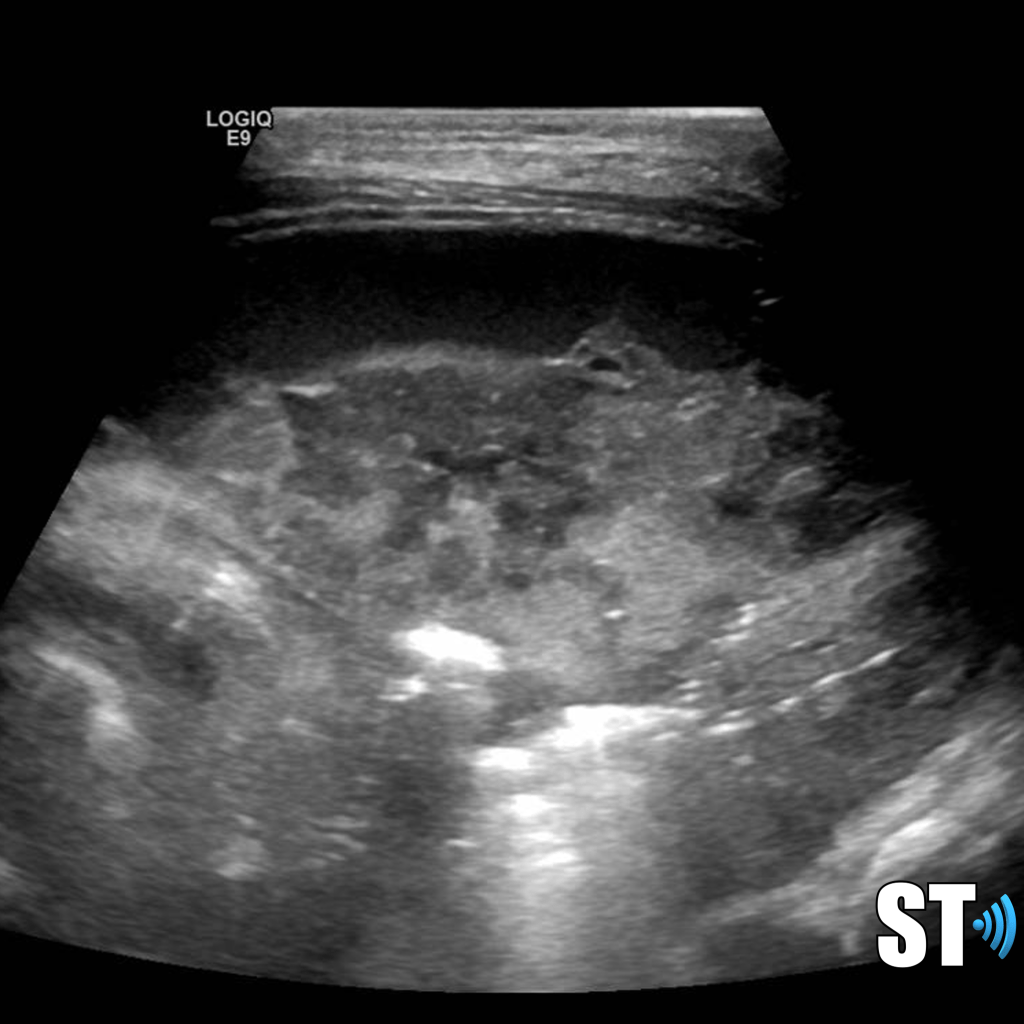

Heterogenous lung with pleural effusion in a patient with necrotizing pneumonia

Necrotizing pneumonia